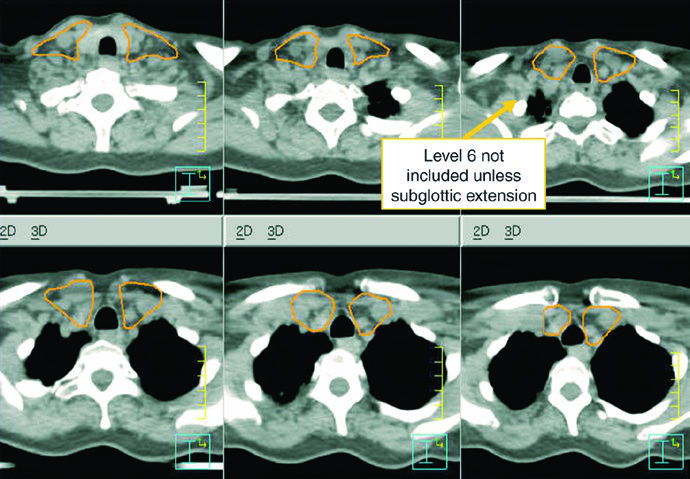

| CTV 54-60a | Should encompass the entire GTV. Includes the entire larynx, from the bottom of the hyoid or the top of the thyroid notch to the bottom of the cricoid cartilage, with further inferior extension when needed. High-risk nodal regions include levels II-IV and the retrostyloid space on the involved node-positive neck. In the node-positive neck, level II should be treated to the base of skull. Level VI should be included if there is subglottic extension or a trach. |

| CTV 54b | Levels II-IV of the uninvolved neck. In the node-negative neck, the superior border of level II stops where the posterior belly of the digastric crosses the internal jugular vein, or at the caudal edge of the lateral process of C1. Levels IB and V are not included unless there is gross disease at those levels. Retropharyngeal nodes may be covered at physician discretion on the side of bulky adenopathy because of retrograde flow. Level VII coverage is recommended for subglottic extension or hypopharyngeal involvement. |

Levels IB and V are not elective by default and are only included when gross disease is present there. Retropharyngeal nodes may be covered on the side of bulky adenopathy at physician discretion. Level VII is recommended for subglottic extension or hypopharyngeal involvement. That is one of the most useful parts of the chapter because it turns abstract spread patterns into concrete cranial and caudal borders.

The high-risk postoperative CTV receives 60 Gy and should include the operative bed, scar, stoma, and dissected node-positive neck. Positive margins or extracapsular extension may justify a boost to 66 Gy. The undissected node-negative neck may be included as a low-risk CTV to 54 Gy. If there is subglottic extension or an emergent tracheostomy, the stoma may also be boosted to 66 Gy. The chapter makes the anatomy explicit: a stomal recurrence is a tracheoesophageal node recurrence.